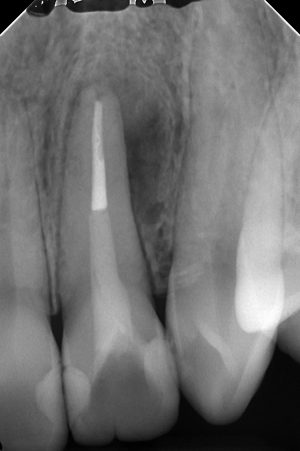

半年後。

かなり治ってくれましたね。

最近、とらびねじゃど先生の『Endodontics principle&practice』という本を読んでいて、術後の評価のセクションで、

『再評価のレントゲンは6カ月ごとにとる。期間が短いと読影が難しい』

ということが書いてあり、まさにその通りだと思います。

しかし、私は3カ月で見ていて、その理由は

『3カ月で跡形もなく病変が消えるケースが結構ある』

というのが理由です。

色々な事情から、レントゲンで治癒傾向が判断つくまで被せ物が被せられないケースがあります。

なので、可能であれば早い段階で、外科に踏み切るか、被せ物を作るか、判断したいケースが少なくないのです。

予後の判断は中々難しいですね。